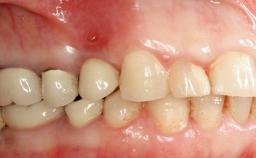

The fracture of an implant after it has been restored is one of the most severe complications. It most frequently occurs in partially edentulous jaws (1.5%). Most implant fractures involve implants with a diameter of 3.75 mm made of commercially pure titanium (Eckert 2010). Unfortunately, many cases are not reported or documented by the clinicians involved in resolving the problems created by the fracture. This case report describes the management of an implant fracture at site 36 in a middle-aged male patient. The implant had been restored with a screw-retained metal-ceramic crown.

Retention Screw-retained Screw-retained